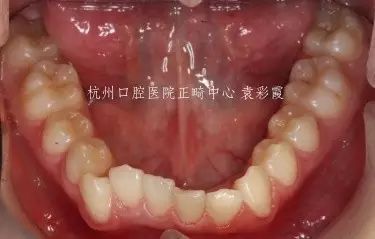

这是我的一例深覆合小患者,儿子完全遗传了父亲的深覆合。

儿子

父亲